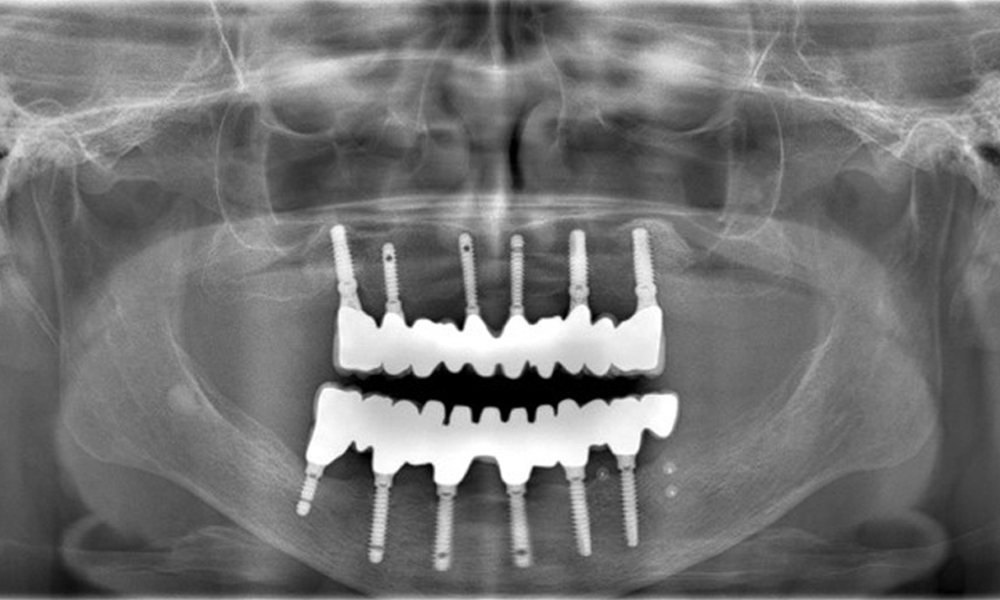

A 74-year-old patient presents for a consultation. The anamnesis shows that the patient has well-controlled hypertension and is taking Lixiana. Additionally, the patient had a kidney carcinoma in 2020. The patient’s lifestyle is unremarkable. She has no natural teeth left and has six implants in both the upper and lower jaws, which are fitted with crowns or bridges. Current findings show no peri-implant mucositis or peri-implantitis; however, there are occasional minor bleeding at the implant sites.

Provisions: Implants in regions 011, 013, 015, 021, 023, 025, 031, 033, 035, 042, 044, 046

The use of Lixiana represents a risk factor; therefore, the complication risk is considered moderate. The oral health is stable and good. To detect potential peri-implantitis early, probing depths (PD) should be measured during follow-up appointments. If there is an increase in PD at the implant compared to the baseline, combined with diffuse bleeding, radiographic diagnostics (e.g., dental X-rays) should be pursued.